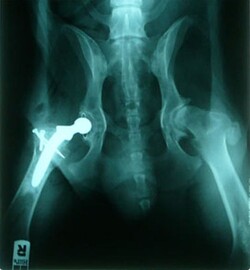

- ortopedie, traumatologie, totální endoprotézy kyčelních kloubů